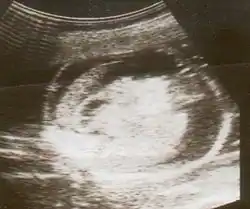

An ultrasound showing a fetus with hydrops fetalis | |

Hydrops fetalis can be diagnosed and monitored by ultrasound scans.[1] An official diagnosis is made by identifying excess serous fluid in at least one space (ascites, pleural effusion, of pericardial effusion) accompanied by skin edema (greater than 5 mm thick). A diagnosis can also be made by identifying excess serous fluid in two potential spaces without accompanying edema. Prenatal ultrasound scanning enables early recognition of hydrops fetalis and has been enhanced with the introduction of MCA Doppler.[7]